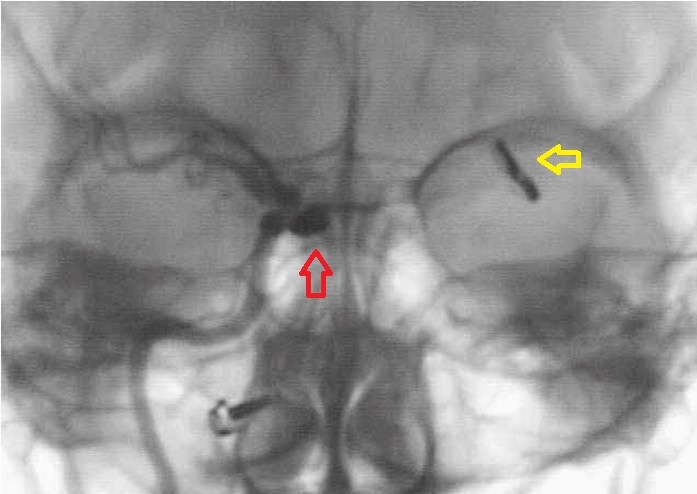

Vasospasmo

all'angiografia. |

Risoluzione

del vasospasmo. |